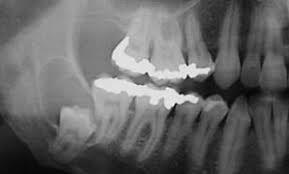

16-year-old, Female, Cyst Associated With Unerupted Lower Wisdom Tooth.

Case 5- Salient points • Non-specific thin squamous epithelial lined cyst • No keratinisation, basal palisading • Largely uninflamed fibrous cyst wall • Location + histology

??

Case 5 Diagnosis

Dentigerous cyst